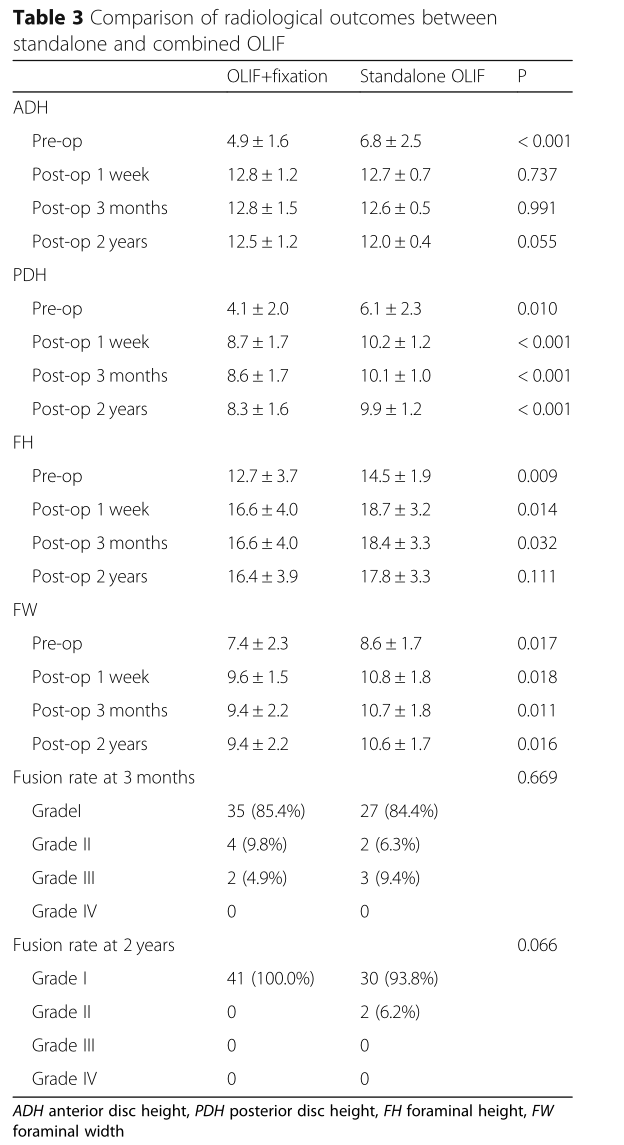

随访2年,VAS和ODI评分无差异,但独立OLIF在1周和3个月时评分更好(P <0.05)。与独立的OLIF组相比,手术前和手术后OLIF组的PDH和FW较小(all P <0.05)。两组之间在术前,第1周和第3个月时的FH有显着差异(all P <0.05),但在第2年时差异消失(P =0.111)。

OLIF联合治疗组分别在3个月和24个月时发生cage下陷,分别为7.3%(3/41)和7.3%(3/41),而6.3%(2/32)和15.6%(5 / 32)分别在独立的OLIF组中的相同时间点显示(P = 0.287)。两组在2年时均没有退笼。3个月时,联合OLIF组的融合率为85.4%(35/41),而独立OLIF组的融合率为84.4%(27/32)(P = 0.669)。在24个月时,联合OLIF组的融合率为100.0%,而独立OLIF组的融合率为93.8%(30/32)(P = 0.066)。